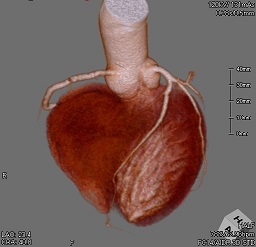

生まれのブランドで I19-175 2017年第10号10月号 臨床放射線 臨床医学